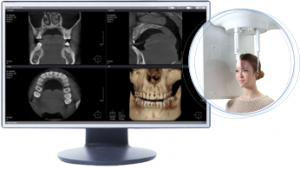

Il Tomografo Cone Beam (detto anche CBCT Tomografia Computerizzata Cone Beam) è un macchinario in grado di ottenere immagini del massiccio facciale attraverso l’emissione di una dose molto bassa di raggi X, restituendo immagini 3D di altissima qualità delle ossa mascellari e dei denti.